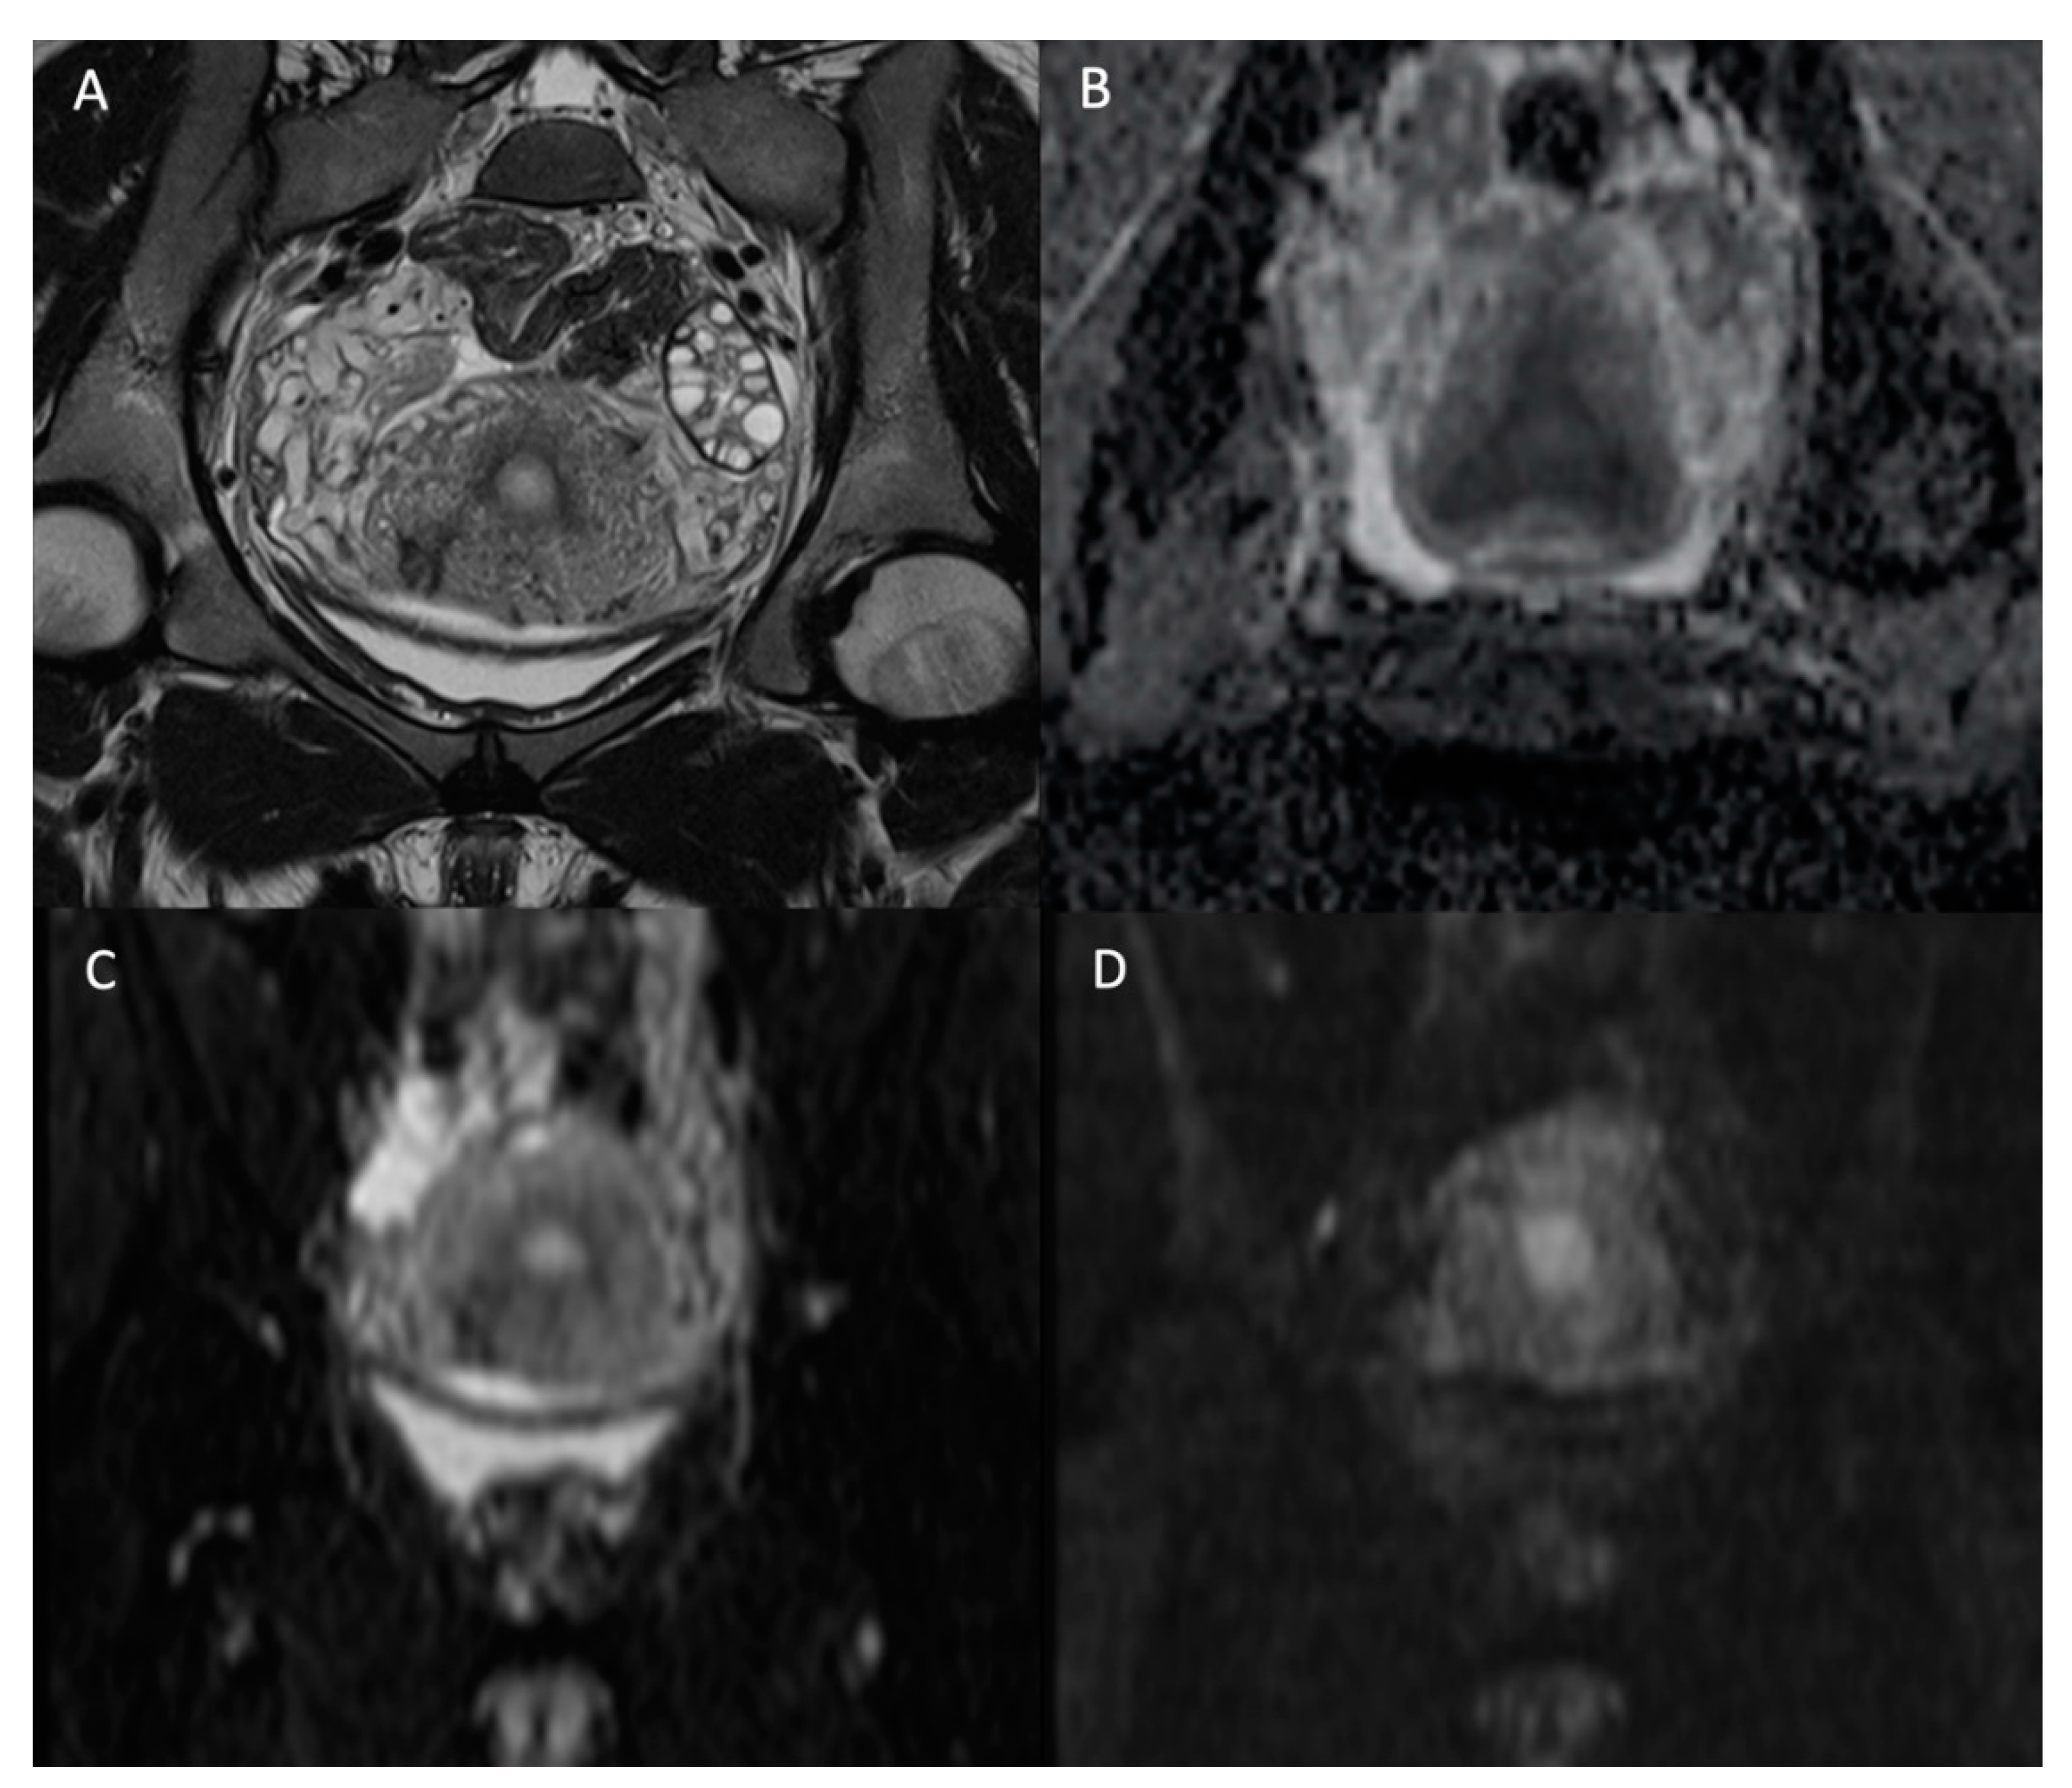

Magnetic resonance imaging is a complementary imaging modality usually performed after an ultrasound. DWI is crucial and performed in most female pelvic studies in addition to conventional morphologic T1- and T2-Weighted (T2W) sequences, as shown in Figure 1. DWI, together with dynamic contrast-enhanced (DCE) imaging, is part of the functional imaging apparatus which in recent times increased the diagnostic performance of MRI in the field of gynecologic oncology. As DWI suffers from poor spatial resolution, and therefore, less anatomical definition, it has to be used in association with a morphologic T2W sequence [15]. DWI is particularly useful in the assessment of endometrial and cervical cancer, helping to differentiate between benign and malignant uterine or ovarian lesions and assessing the peritoneal tumor extension of gynecologic cancers [16].

Figure 1.

Normal female pelvis of 26-year-old in the coronal plane. (A) T2W image; (B) ADC map; (C) b-value = 0 s/mm2 DW image; (D) b-value = 1000 s/mm2 DW image. We see the disappearance of high fluid signal (as the one in the bladder) with increasing b-values but persistence of high signal intensity on high b-value for the endometrium.